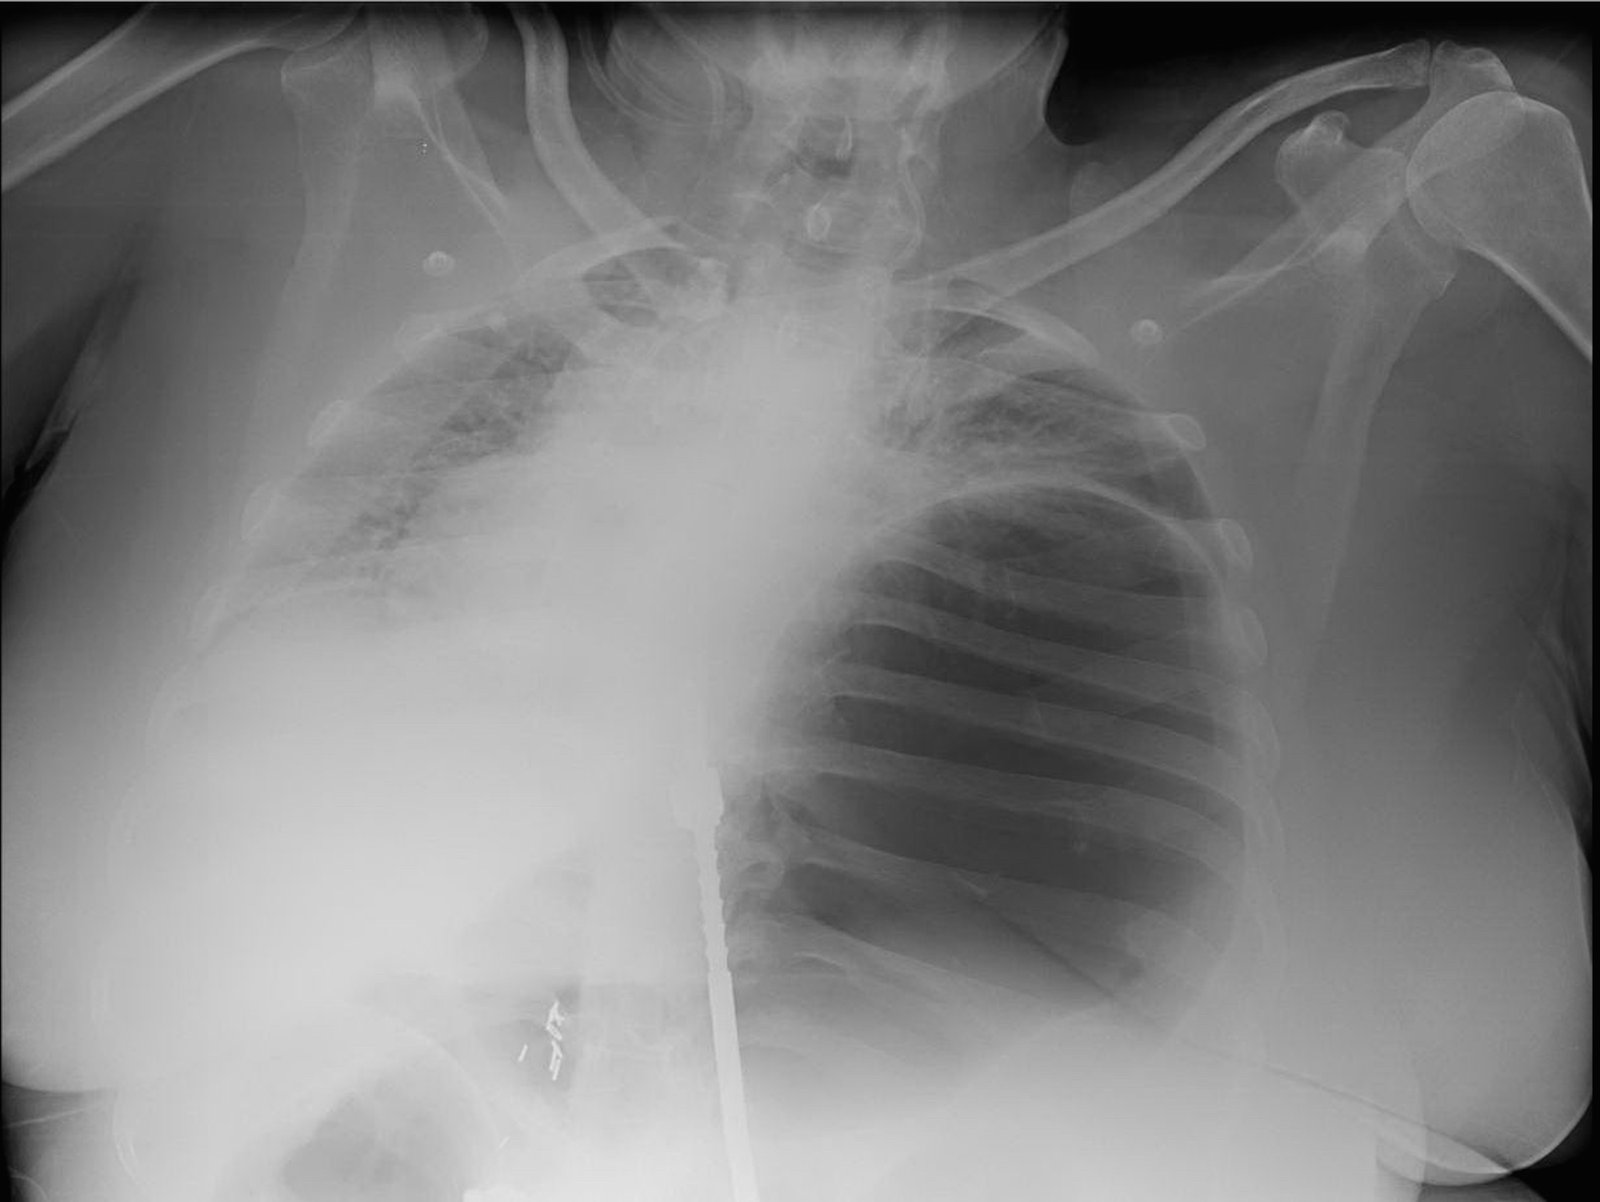

Gastrothorax XRay. JETem 2017

An Elderly Female with Dyspnea and Abdominal Pain